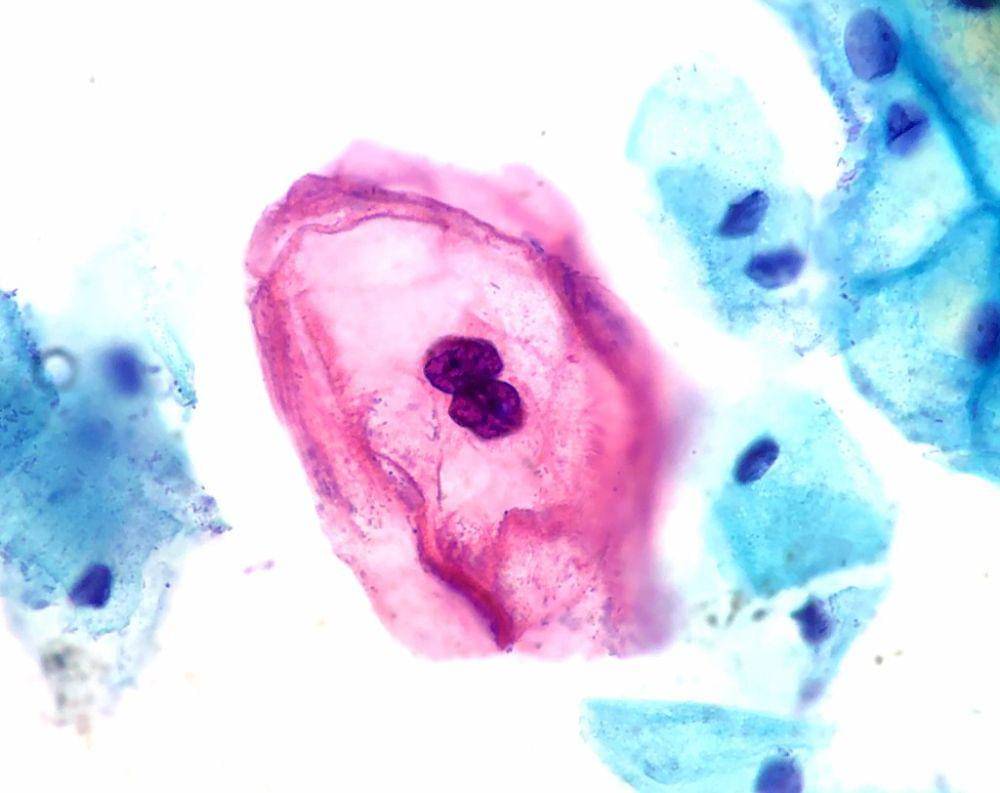

2. Keputihan abnormal

Keputihan yang abnormal juga termasuk dalam gejala kanker serviks stadium awal. Ketika hal ini terjadi, tampilan warna lendir pada keputihan terlihat tidak biasa dan beraroma tidak sedap. Selain itu, tekstur dan konsistensi cairan vagina juga terasa tidak biasa.